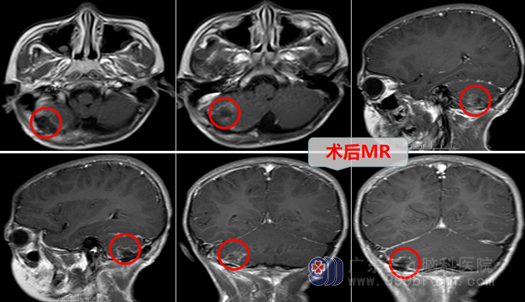

从今年5月开始,8岁10个月的小豪,反复头痛并越来越严重了,感昏昏沉沉,癫痫也更频繁的发作,一个星期就1-2次小发作,这可急坏了他的爸爸妈妈,无奈小豪爸爸妈妈带着小豪换到了广州另外一家医院,另外的医院建议小豪做个头部MR,不做不知道,一做这可吓坏小豪的父母了:小脑半球出血?,焦急万分且万般无奈的小豪妈妈,听到亲戚的建议立即带着小豪驱车赶来了广州,他们慕名来到了专业的脑科医院—广东三九脑科医院,神经外十科。小豪妈妈一直很紧张跟焦虑,她不知道在这里能否找到救她儿子的人。经过全面检查,收治小孩的恰是他的老乡—神经外十科的冯桂栗医生。经过一系列的检查,小孩的头颅CT示:“右侧小脑半球出血,考虑血管瘤(畸形)出血?”,通过阅片,冯医生惊奇的发现小豪脑袋里面长了一颗肿瘤(海绵状血管瘤),初步诊断为:1.右小脑海绵状血管瘤(畸形)伴蛛网膜下腔出血,而这颗肿瘤如果再长大、再出血就可能会要了小孩的命,而且更不巧的是小豪心脏检查也有问题,窦性心动过缓,异常心电图。外十科欧阳辉主任查房指示:24小时EEG动态观察后,再决定下一步治疗,所幸结果出来小豪的动态心电和超声心动图并没有什么大碍。

6月25日,欧阳辉教授决定:全麻下为小豪进行了右侧小脑半球病损切除术,就这样小豪被送进去的手术室,在欧阳教授领导下,由于外十科团队的技术精湛,经过医生几个小时的奋战,小豪当天下午14:00就完成了手术。

回到病房,小豪异常的精神,跟没手术前精神状态一样,手脚活动都没问题,再也没有癫痫发作了,还当天拔除了尿管。小豪妈妈喜出望外,一直给手术医生及孩子竖起大拇指,也对外十科的医生护士团队表示非常满意,太感谢外十团队的医生护士了!看到小豪一家人其乐融融,面带笑容,医生护士们也感到很欣慰,期待小豪顺利康复出院。6月26日,欧阳主任查房指出:患儿小脑海绵状血管瘤(畸形)伴出血,已经行手术治疗,原右侧小脑半球海绵状血管畸形已切除、血肿已经清除,CT术呈术后改变,手术完全成功,达到目的,准备让患儿出院。